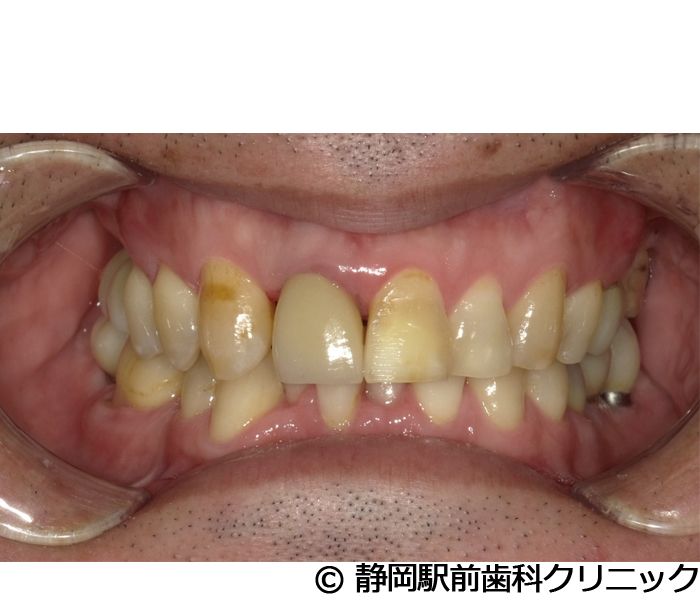

【症例5】全顎的インプラントとセラミックによる審美補綴

- 治療前

- 治療後

- 治療名

- 全顎的インプラントとセラミックによる審美補綴

- 費用

- 1,800,000円(税込)

- 期間

- 1年6ヵ月

治療内容

患者様の症状

全体的に歯がないため、噛めない。インプラント治療希望。

治療方法

全体的に残根は抜歯を行い、術前にCTを撮影し緻密に治療計画を立てた。インプラント埋入はブロックごとに行い、噛み合わせの調整を重ねた後、人工歯を被せて咬合と審美の回復を行いました。

治療結果

しっかり奥歯で食べ物を噛み切ることができるようになり、何でも食べることができるようになったと喜んでいただくことができました。口元を気にせずに笑うこともできるようになり、見た目もキレイになったとご満足いただけました。

※治療結果は個人差があります。

治療を行う上での注意点(リスク・副作用)

術後は、出血、腫れ、痛みなどが出る可能性があります。